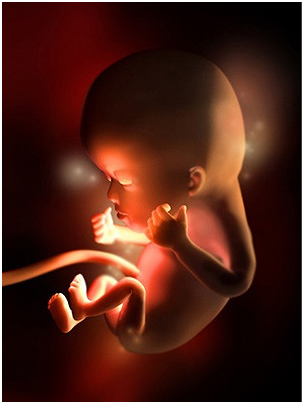

胎儿图

胎儿发育

本周已能够清晰地看到胎儿脊柱的轮廓,脊神经开始生长。你的子宫现在看起来象个柚子,借助多普勒仪器,你可以听到胎儿心脏快速跳动的声音,有些孕妇称之为快速奔跑的小马。

胎儿身长已经达到4-6厘米,体重达到14克,开始能做吸吮、吞咽和踢腿动作,在本周胎儿的很多细微之处也开始出现,可清晰的看到手指、脚趾和绒毛状的头发等。胎儿维持生命的器官如肝脏、肾、肠、大脑以及呼吸器官都已经开始工作。